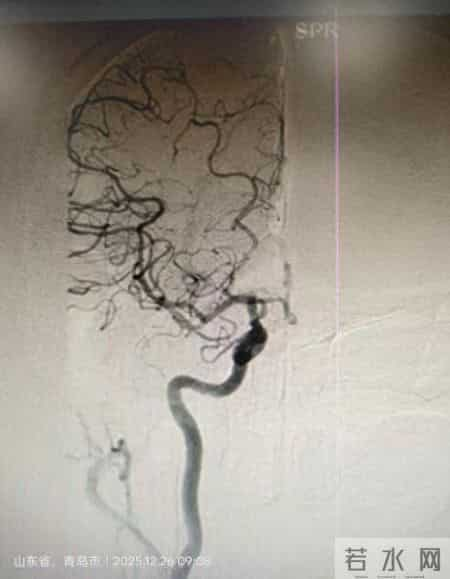

刘文华副主任医师会诊后,神经内科立即启动卒中绿色通道,争分夺秒完成检查与评估。初步诊断为右侧大脑中动脉闭塞,给予静脉溶栓后,立即桥接治疗,并迅速制定了“右侧大脑中动脉取栓术”的紧急手术方案。

手术台上,神经介入团队配合默契、操作有序。首先通过取栓支架达到闭塞位置,抽吸导管精准到位,采用抽拉结合的方式,不到40分钟,一把完全取出堵塞的血栓。随着大脑中动脉血管的成功完美再通,脑部供血迅速恢复。患者术后效果立竿见影,神志转清,言语清晰,左侧肢体肌力更实现了从0级到4级的跨越性提升,肢体功能显著改善,成功避免了残疾的严重后果。